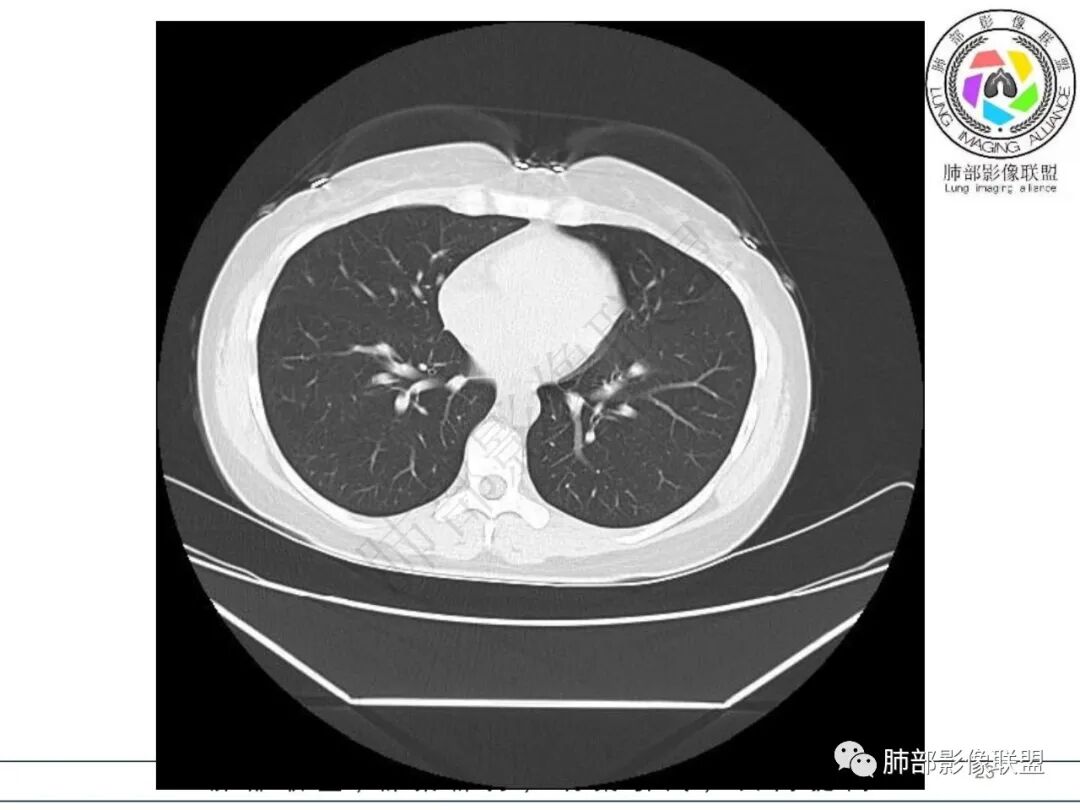

1.临床病史:急性病程,发热畏寒,乏力纳差,恶心呕吐,白细胞不高,CRP及血沉升高。

2.影像特征:右肺下叶局限性实变影伴晕征,边界不清,内部支气管尚通畅,实变区密实区边缘稍膨隆。符合炎性病灶特征。

3.综合分析:急性病程,炎性指标高,常见的是普通社区肺炎,如肺炎链球菌感染等。但本例患者临床表现较重,应先表现相对较轻,白细胞不高,须考虑非典型肺炎的可能性。本例隐球菌荚膜实验阴性,而军团菌临床症状一般较重,影像分布也更广泛、进展迅速,多器官损害更明显。因此考虑鹦鹉热衣原体可能性更大一些。其他如腺病毒等感染也是需要排除的。

最终支气管镜灌洗NGS确诊为鹦鹉热衣原体感染。